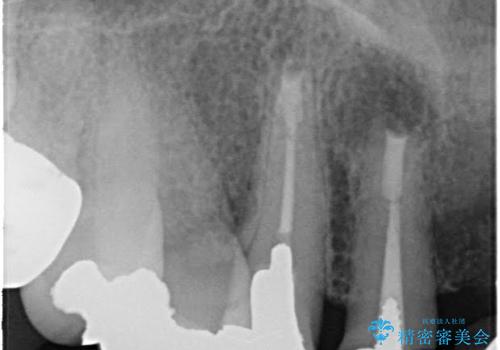

- 仮歯の製作、古い土台(メタルコア)の除去まで行い、根管治療は専門医に依頼

→根管治療終了後、ファイバーコアを築造し、新しいセラミックブリッジを製作した。

一見きれいにはいっているセラミックも、はずして中の状態をみるとひどいことが多い。これは、中の土台の状態や処理のクオリティは、短期的には問題を起こしづらく、患者さんには見えない部分だからです。